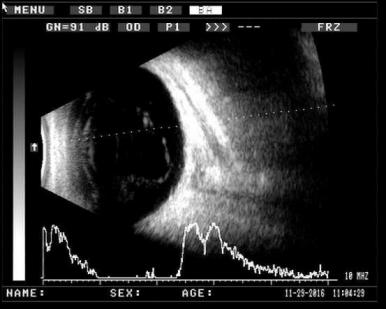

? 飛蚊癥的在B超上的表現為玻璃體內可探及多個不規則形弱點狀,條帶狀回聲。如下圖所示:

圖1??玻璃體內條帶狀回聲

圖2??玻璃體內點狀回聲